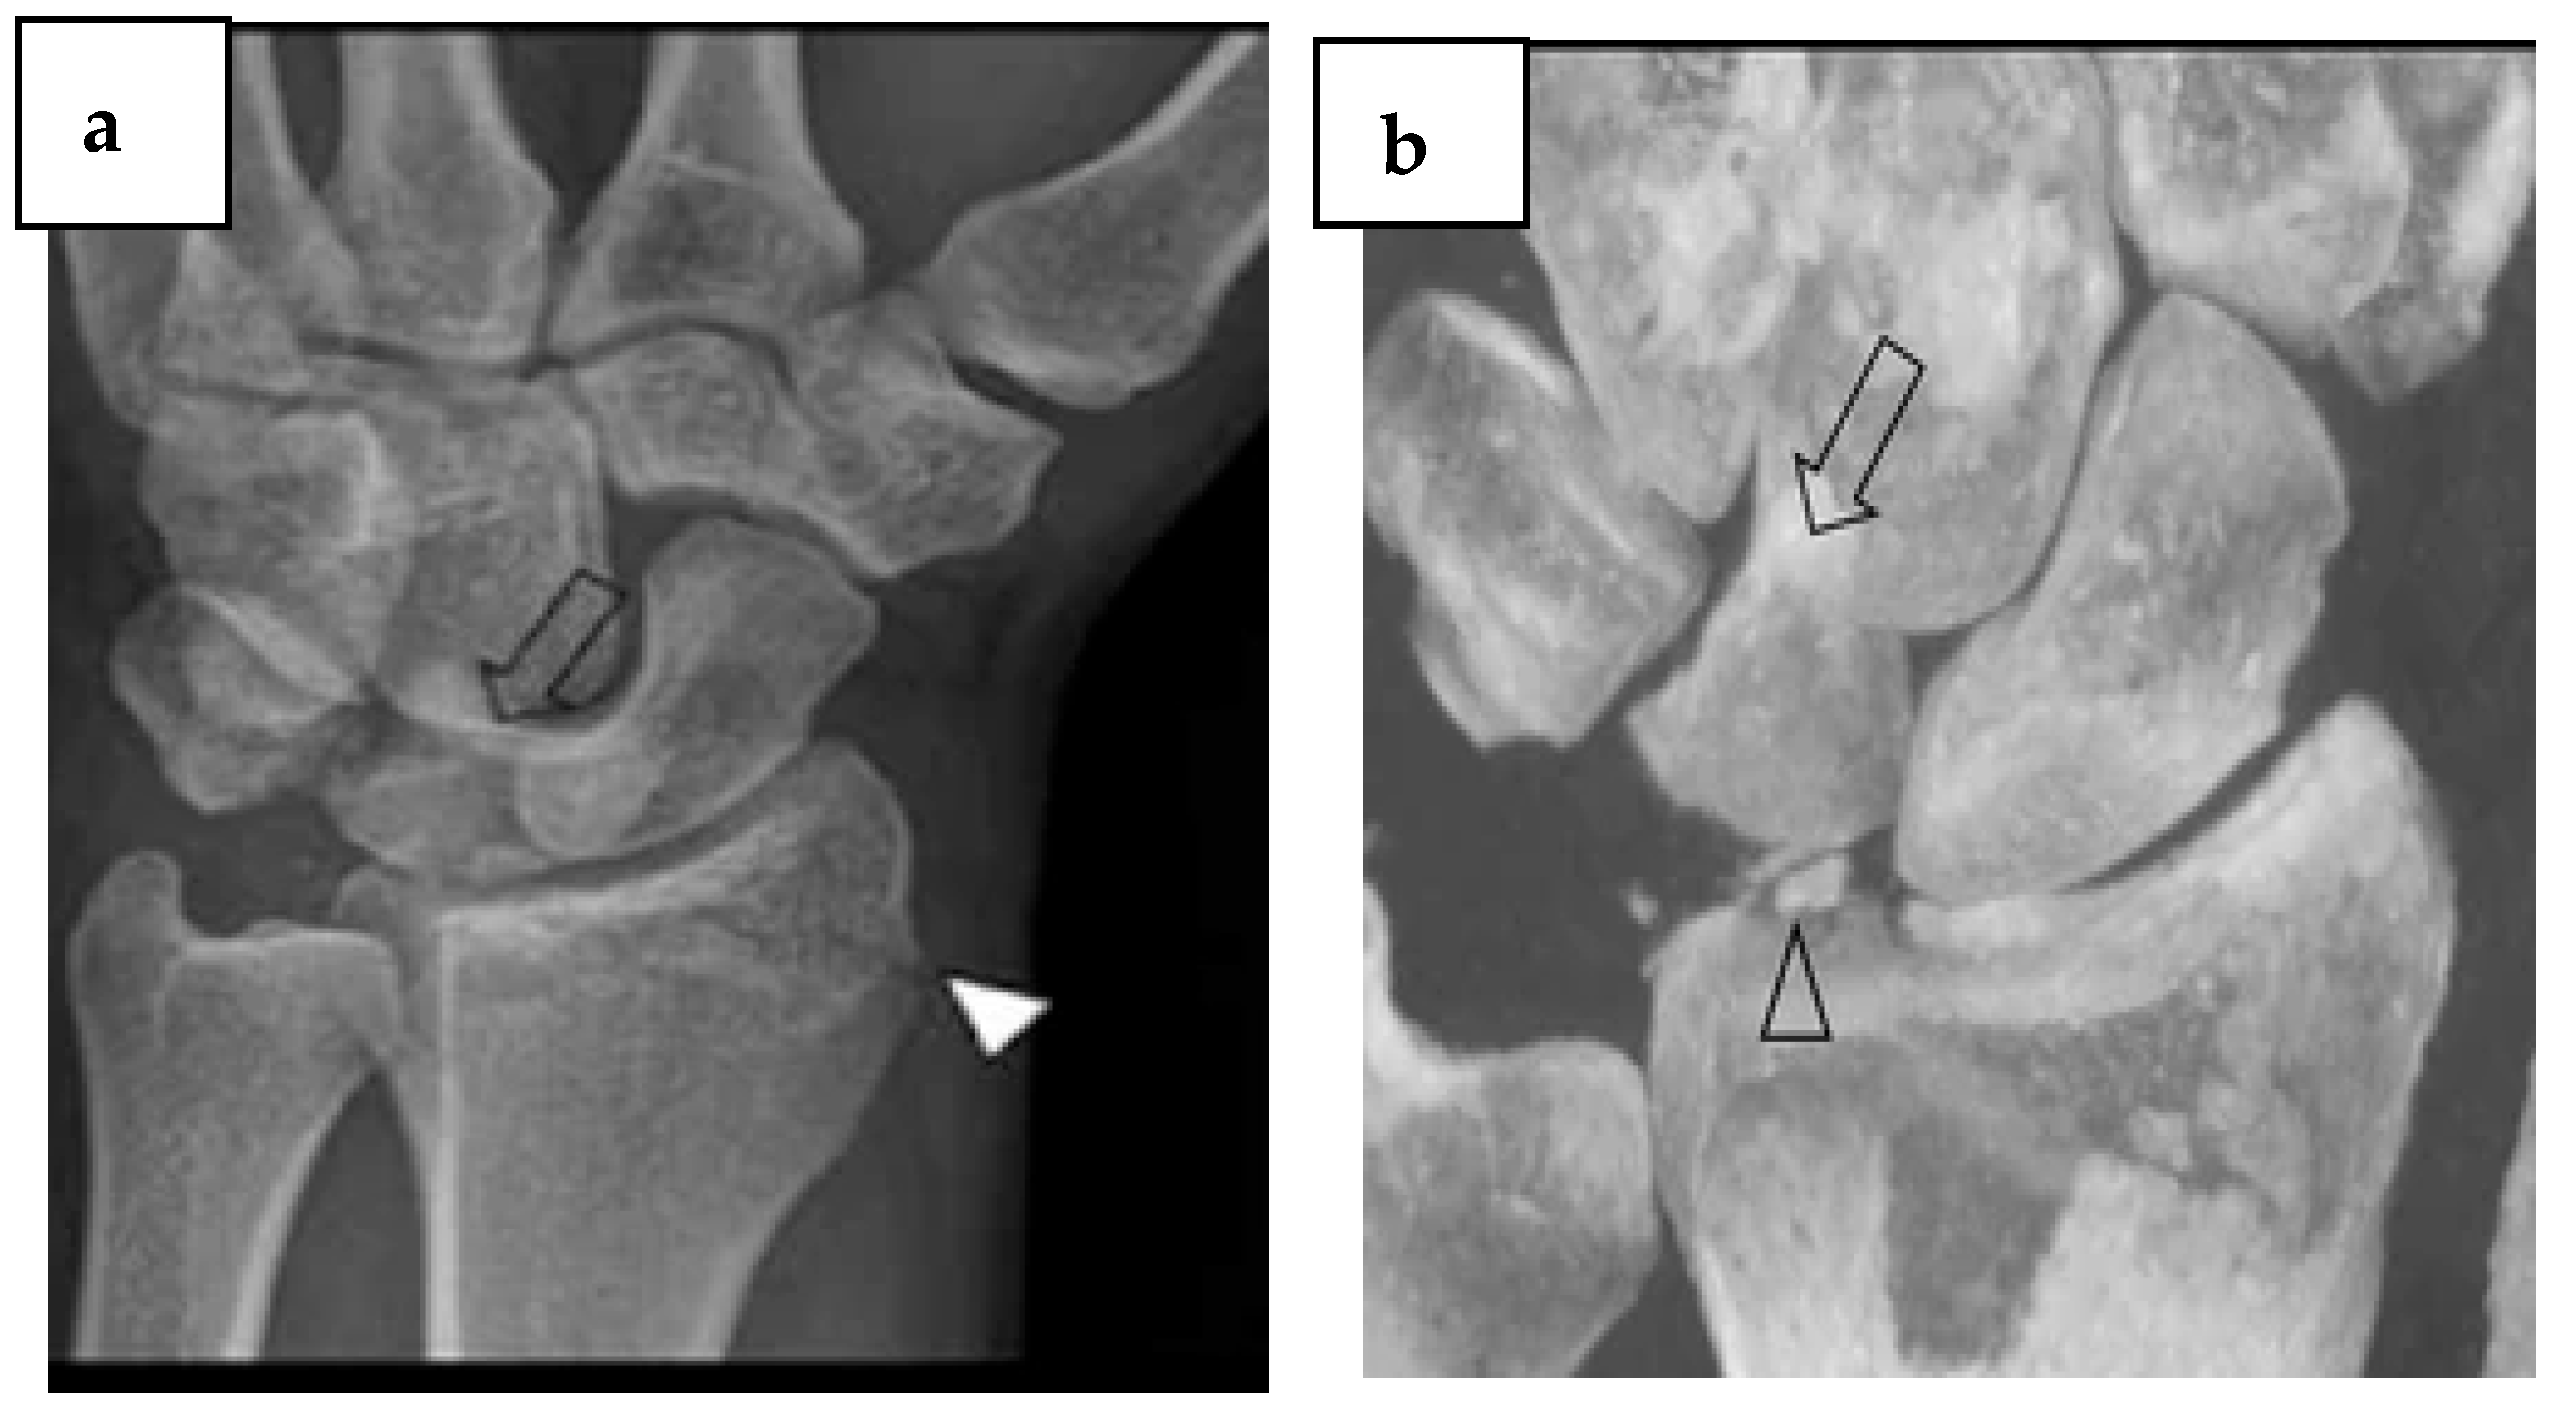

- Vanhoenacker, F.M.; Desimpel, J. Cone Beam CT of Trauma of Small Bones and Joints. Semin Musculoskelet Radiol 2017, 21, 290–302. [Google Scholar] [CrossRef] [PubMed]

- Czarnecki, P.; Siemionow, M.; Baek, G.H.; Górecki, M.; Romanowski, L. Hand and wrist–what the hand surgeon wants to know from the radiologist. Pol. J. Radiol. 2024, 89, e70. [Google Scholar] [CrossRef] [PubMed]

- Edlund, R.; Skorpil, M.; Lapidus, G.; Bäcklund, J. Cone-Beam CT in diagnosis of scaphoid fractures. Skelet. Radiol. 2016, 45, 197–204. [Google Scholar] [CrossRef] [PubMed]

- De Smet, E.; De Praeter, G.; Verstraete, K.L.A.; Wouters, K.; De Beuckeleer, L.; Vanhoenacker, F.M.H.M. Direct comparison of conventional radiography and cone-beam CT in small bone and joint trauma. Skelet. Radiol. 2015, 44, 1111–1117. [Google Scholar] [CrossRef] [PubMed]